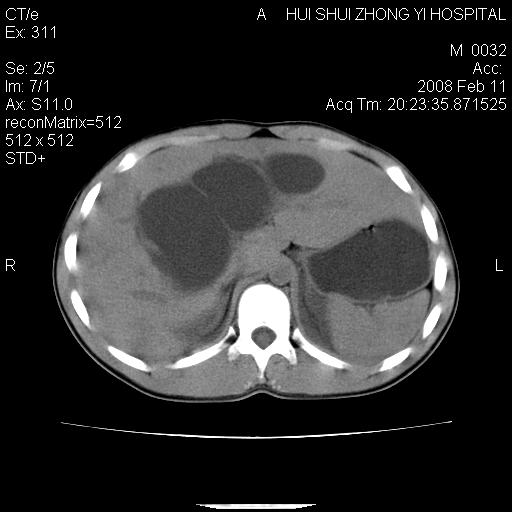

8年前曾在贵洲省人民医院b超诊断为肝内胆管结石。现腹痛剧烈,现发烧、头痛、恶心呕吐县医院b超示胆囊肿大大小159*46mm,囊内见6*5mm强回声光团,胆各总管内径56mm。提示:胆囊结石、急性胆囊炎、胆总管重度扩张。

胆囊结石.急性胆囊炎.重度胆管扩张.右侧胸腔少量积液,建议ct增强

考虑先天性胆管囊肿;胆囊增大并结石。右侧胸腔少量积液,建议ct增强。

caroli囊肿并囊内结石。胆囊增大并胆结石。典型!

先天性胆管囊肿,胆囊结石、胆囊增大,右侧少量胸腔积液。